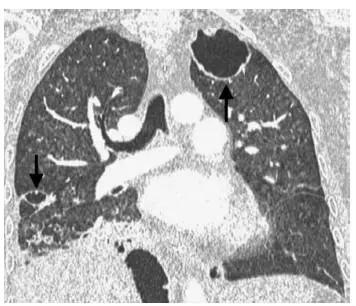

这事儿真不是吓唬人。这男生连续咳嗽、发烧一个多月,硬撑着没当回事,直到咯血才慌神去医院。结果CT片子出来,医生都惊了——整个肺像被虫子蛀过一样,布满了空洞。

你猜怎么回事?竟然是结核杆菌在作祟。这玩意儿专门“啃”肺,小伙子长期熬夜打游戏,免疫力下降,正好给了病菌可乘之机。